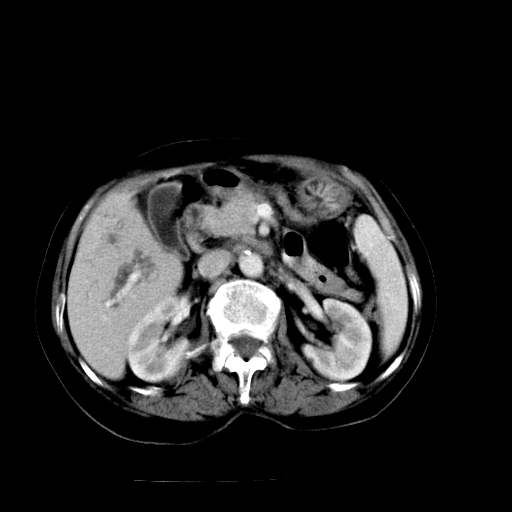

以下是引用随光逐影在2009-4-7 8:21:00的发言:[br]肝内外胆管多发性结石并肝内外胆管扩张;胆系感染。